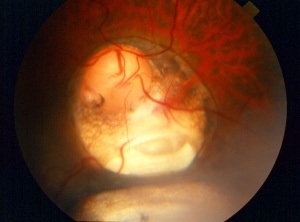

Posteriorly located coloboma can involve the optic nerve, retina, and choroid. If the retina is involved, it is reduced to glial tissue with no underlying RPE or choroid. This appears as an area of whitening often with pigment deposition at the junction of the coloboma and normal retina. If the optic nerve is involved, it can have a range of appearance from physiologic cupping to extensive retinal involvement (as shown in the figure below). The examiner should be wary during initial examination to evaluate for retinal detachment as patients with coloboma have increased risk for this to occur.

Figure 5. Coloboma involving the optic nerve, retina, and choroid in the typical inferonasal quadrants. Photo courtesy of AAO.[20] |